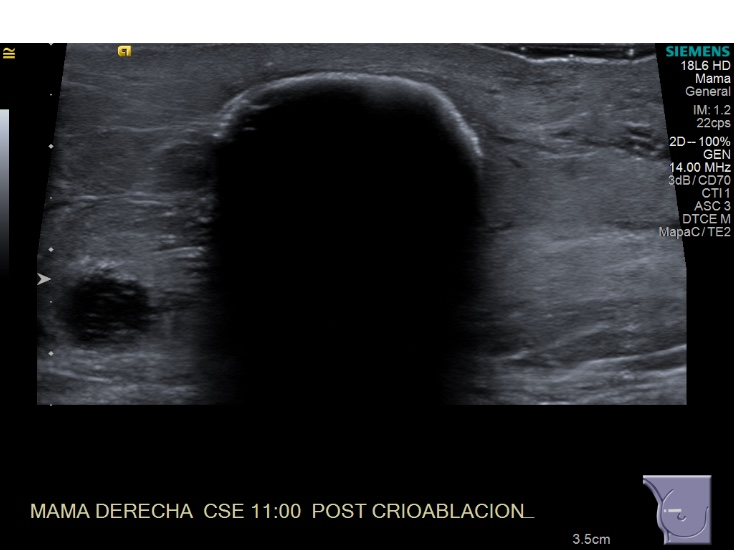

Crioablacion de tumor en mama derecha